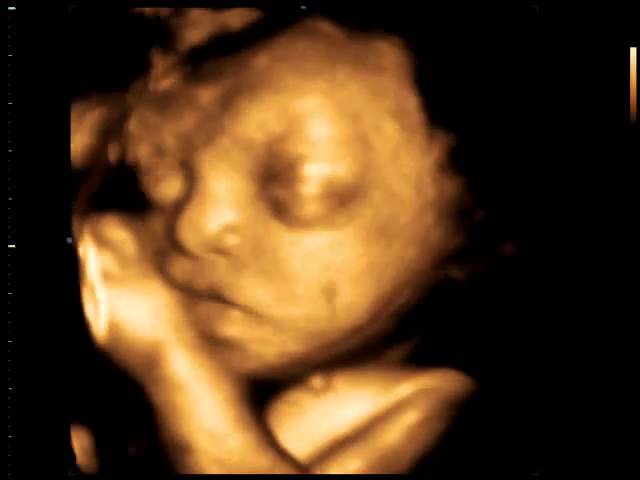

A gestação por si só já é um momento maravilhoso no qual muitas emoções são vividas pelos pais e familiares. Entretanto, o tempo passou e novas tecnologias surgiram para tornar este momento ainda mais especial. Estamos nos referindo à Ecografia em terceira e “quarta dimensão”, a chamada Ecografia 3D/4D.

Ambas mostram detalhes do bebê, tais como contornos e fisionomias. A 4D permite ver o bebê em movimento, sorrindo, bocejando, passando a mão no rosto, abrindo e fechando as mãos entre outras peripécias.

Esta ecografia pode ser realizada em qualquer período da gestação. Entretanto, o melhor período para visualização é entre 25 e 32 semanas, ou seja, entre o sexto e sétimo mês de gestação.

Atualmente, disponibilizamos de tecnologia capaz de oferecer imagens tão reais dos bebês que podemos dizer com quem eles se parecem mesmo antes de nascerem. Podemos acompanhar com detalhes cada passo da formação de uma nova vida.